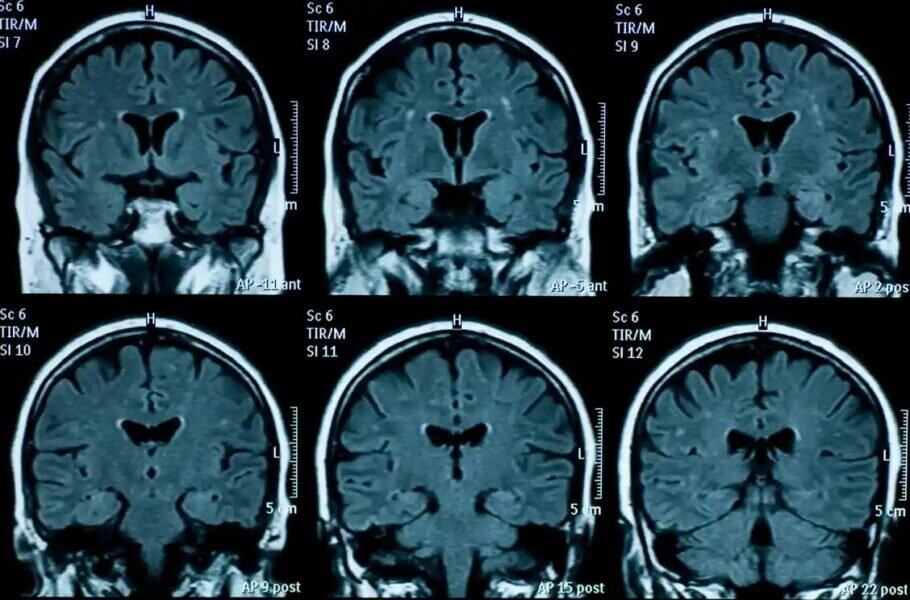

دیجیاتو نوشت: طبق این مطالعه، تغییرات فیزیکی مغز نوجوانان در دوران پس از همهگیری، بسیار سریعتر رخ داده که این امر منجر به پیری زودرس میشود.